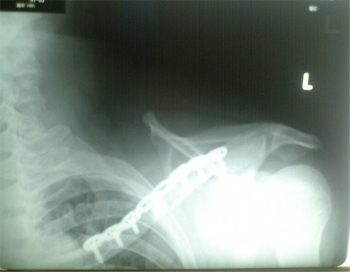

4日(水)病院のベッドでも良く眠れる。手術の日。時間はよくわからないが、とにかく午後だという。11時頃に『午後1時30分予定です。』と看護婦さんに言われると、なんか緊張はするは、昨夜から何も食べてないのでお腹もすくはで、困ったものだ。時間どおり1時30分に病室を出る。手術室に入り、マスクを充てられ、深呼吸を何回かすると麻酔担当の人が『麻酔薬を入れます。』と言ったと思ったら、『ワイルド・チャイルド』が流れてきてが、ほんの2小節くらいしか記憶にない。目が覚めたときは、目の前に先生たちの顔があり、『終わったんですか?』と聞いたら、終わったという返事があり、『あ〜、終わったんだ。』と初めて手術が終わったのを実感した。手術は予定した時間どおりにことが進んだようで、3時30分には手術室を出たらしい。手術室を出て、レントゲン室でレントゲン写真を撮り、ナースス

テーションの隣の部屋に行く。ここはHCUという部屋らしい。ICUの一歩手前という意味なんだろか?執刀してくれた先生も様子を見に来てくれて、レントゲン写真を見せてくれた。『ボルトは6本ですか?』と聞いたら、『横にも入ってるから7本です。』と返事があった。『グー、パーして』というので手を動かすと、『痺れてない?』と聞いてきた。『痺れていない。』と云うと、『腕も上下に少し動かしてね。』といって部屋を出て行った。腕を動かしてみたが、思うようにはいかない。まだ麻酔が抜けきっていないようで、ぼやぁ〜っとしていたのだが、そのうち寝てしまった。ところが夜中に奥のほうでおばあさんらしき人が点滴を無理やりはずしちゃったようで、看護婦さんたちが大騒ぎ。夜中の11時頃と看護婦さんが教えてくれた。なんだろう?思っていたら、そのおばあさんはその後も騒ぎ続け、ボクは眠いのに眠れないし、傷口を冷やす氷枕も重くて痛いし、腰は痛いしで、1時間おきくらいに看護婦さんに面倒見てもらっていた。看護婦さんも『眠れなくてかわいそうね。』と同情してくれて、『早めに部屋に戻しますから。』と云ってくれ、午前5時15分に入院したときの306号室に復帰し、やっと眠れた。が、起床時間の6時には目覚めてしまった。